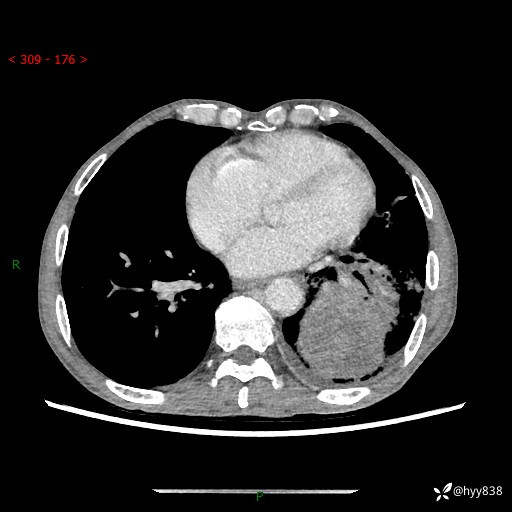

77岁/男,腹痛2月,CT发现左肺占位1天。巨大肿块,肺内或肺外来源…结果公布~

主诉:腹痛2月,CT发现左肺占位1天

现病史:患者于2025年9月间断左下腹胀痛,在当地镇卫生院行彩超检查考虑泌尿系结石,行止痛排石对症治疗未见明显好转;1天前腹痛症状加重,至当地市第三人民医院行CT检查:左肺下叶巨大团块状软组织影,考虑肿瘤性病变,建议增强CT检查;左侧胸腔积液;纵膈内淋巴结肿大;双肺肺气肿;右肺中叶纤维灶。为进一步求治,来我院就诊。

胸部CT平扫+增强